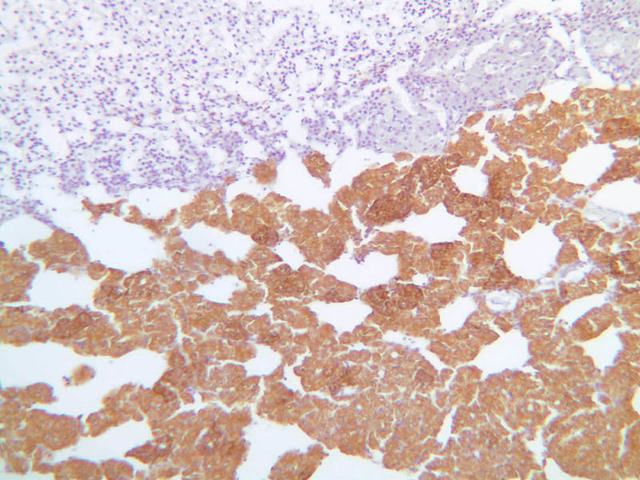

The thyroid gland (slide B-51, lead hematoxylin [10x, 20x, 40x, 40x]; B-52, H&E [10x-labeled, 20x, 40x-labeled, 40x]; B-53, PAS [2.5x, 10x, 20x, 40x]) consists of many closely packed, roughly spherical structures known as follicles, which are enclosed in a thick connective tissue capsule. Connective tissue septa extend from the capsule into the substance of the gland, carrying numerous blood vessels. Follicular cells are arranged as shells of simple cuboidal epithelium surrounding a gelatinous mass known as colloid. Look for a ring of epithelial cells around the homogeneous, pink-staining colloid. The cytoplasm of the follicular cells (principal cells) is faintly basophilic. The follicular cells secrete thyroglobulin, a glycoprotein, which is stored extracellularly in the colloid. In response to TSH, the follicular cells endocytose the colloid and hydrolyze it to form thyroxine. You can see where colloid has been resorbed because this process leaves small holes in the colloid adjacent to the follicular cells. These holes are known as resorption lacunae (B-52 [10x, 20x, 40xlabeled]). Very active follicles may exhibit a columnar epithelium and increased numbers of resorption lacunae. Between follicles, the stroma of the thyroid gland consists of a thin layer of connective tissue and a rich capillary network. Parafollicular cells (light cells or C cells) are located in the connective tissue between follicles or adjacent to follicular cells within follicles. When they lie within the follicular wall, the parafollicular cells do not reach the lumen. Parafollicular cells are slightly larger than the follicular cells and, in H & E preparations, have a more lightly stained cytoplasm (B-52, H&E [10x, 20x, 40x-labeled] [10x-labeled, 20x, 40x-labeled] [10x, 20x, 40x] [10x, 20x, 40x]; B-53, PAS [10x, 20x, 40x]). Parafollicular cells are readily identifiable in slide B-51 (stained with lead hematoxylin), where they appear as purplish-black structures in which the nuclei are difficult to discern (B-51 [10x, 20x, 40x-labeled]). These cells secrete calcitonin, which lowers serum calcium levels by inhibiting bone resorption and accelerating osteoid calcification.